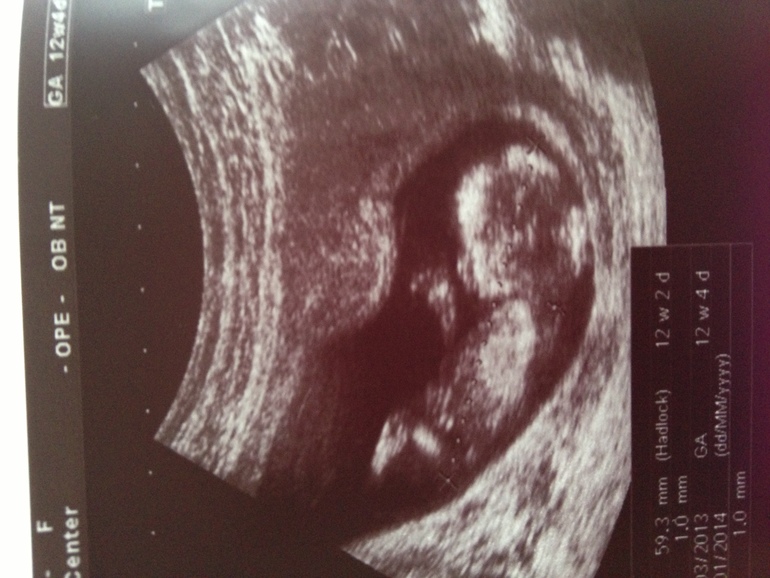

Первое фото :)

беременностьРешила поделиться первой фотографией :) Повернуть ее почему-то не могу, не разобралась еще как тут и что )) Но, надеюсь и так понятно,))

12 недель 4 дня